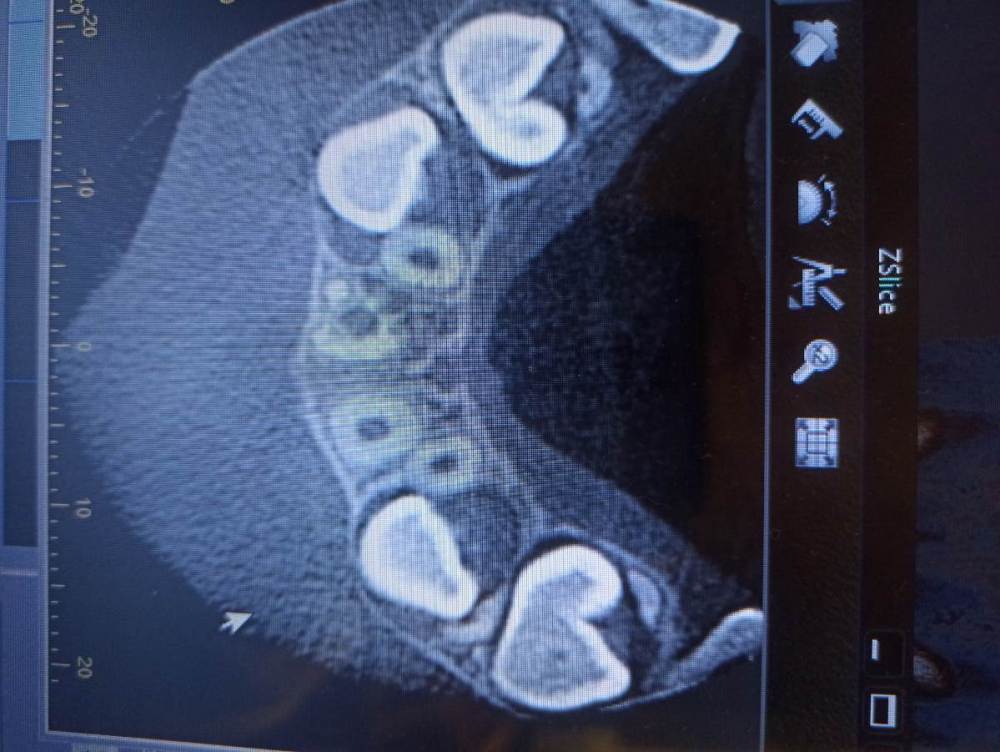

Pole4ka Опубликовано 4 июля, 2021 Автор Поделиться Опубликовано 4 июля, 2021 Так выглядит в живую. 16 минут назад, red_butler сказал: Здравствуйте, сказать что то конкретное только по вашим снимкам не возможно. Нужен очный осмотр и Кт Если можно, посмотрите пожалуйста снимки КТ. Спасибо огромное! Ссылка на комментарий

wladdX Опубликовано 4 июля, 2021 Поделиться Опубликовано 4 июля, 2021 Насколько могу судить по приложенным скринам, резорбция корня всё же есть. Судя по Вашему рассказу, проведённая коллегами работа была верной, результат весьма неплохой. Рассчитывать на длительное пребывание зуба 11 в челюсти не приходится. Когда-то его придётся удалить. 1 1 Ссылка на комментарий

Pole4ka Опубликовано 4 июля, 2021 Автор Поделиться Опубликовано 4 июля, 2021 38 минут назад, wladdX сказал: Насколько могу судить по приложенным скринам, резорбция корня всё же есть. Судя по Вашему рассказу, проведённая коллегами работа была верной, результат весьма неплохой. Рассчитывать на длительное пребывание зуба 11 в челюсти не приходится. Когда-то его придётся удалить. Спасибо большое за Ваше мнение и отклик! Нам бы дотянуть до момента, когда можно будет ставить имплант. Честно говоря, особой разницы между прошлогодним снимком (нижним среди снимков) и панорамным не вижу, поэтому возникла надежда, что резорбция приостановлена. А анкелоза нет? Спасибо! @wladdX Спасибо!!! Ссылка на комментарий

wladdX Опубликовано 5 июля, 2021 Поделиться Опубликовано 5 июля, 2021 Резорбция корня + вертикальное расположение = анкилоз. То что зуб был с несформированной верхушкой корня помогло ему простоять так долго после реплантации в растущей челюстной кости. Конечно, хорошо бы, чтоб зуб смог простоять до имплантации, но на мой взгляд это маловероятно. 1 1 Ссылка на комментарий

Bier Опубликовано 6 июля, 2021 Поделиться Опубликовано 6 июля, 2021 Я вас не порадую: 1. Зуб анкилозирован. 3 часа в физрастворе = нет шансов на реваскуляризацию пульпы и связки. Судя по вашим снимкам однозначно анкилозирование. 2. Что делать теперь и почему: Зуб начал отставать в росте, еще через несколько лет это превратится в нерешаемую эстетическую проблему (вся челюсть будет расти, а зуб и участок челюсти с зубом - нет). Необходимо провести операцию декоронации (спилить коронковую часть зуба глубже уровня костной ткани, удалить то, что осталось от пульпы и дать так зажить. Остатки корня резорбируются сами с замещением на кость. Зато челюсть будет расти вместе с отстальными зубами. восстановить зуб временно на пластике (съемной) потом на брекетах. Имплантация желательно не раньше 21 года. Оставлять так нельзя! Ссылка на комментарий